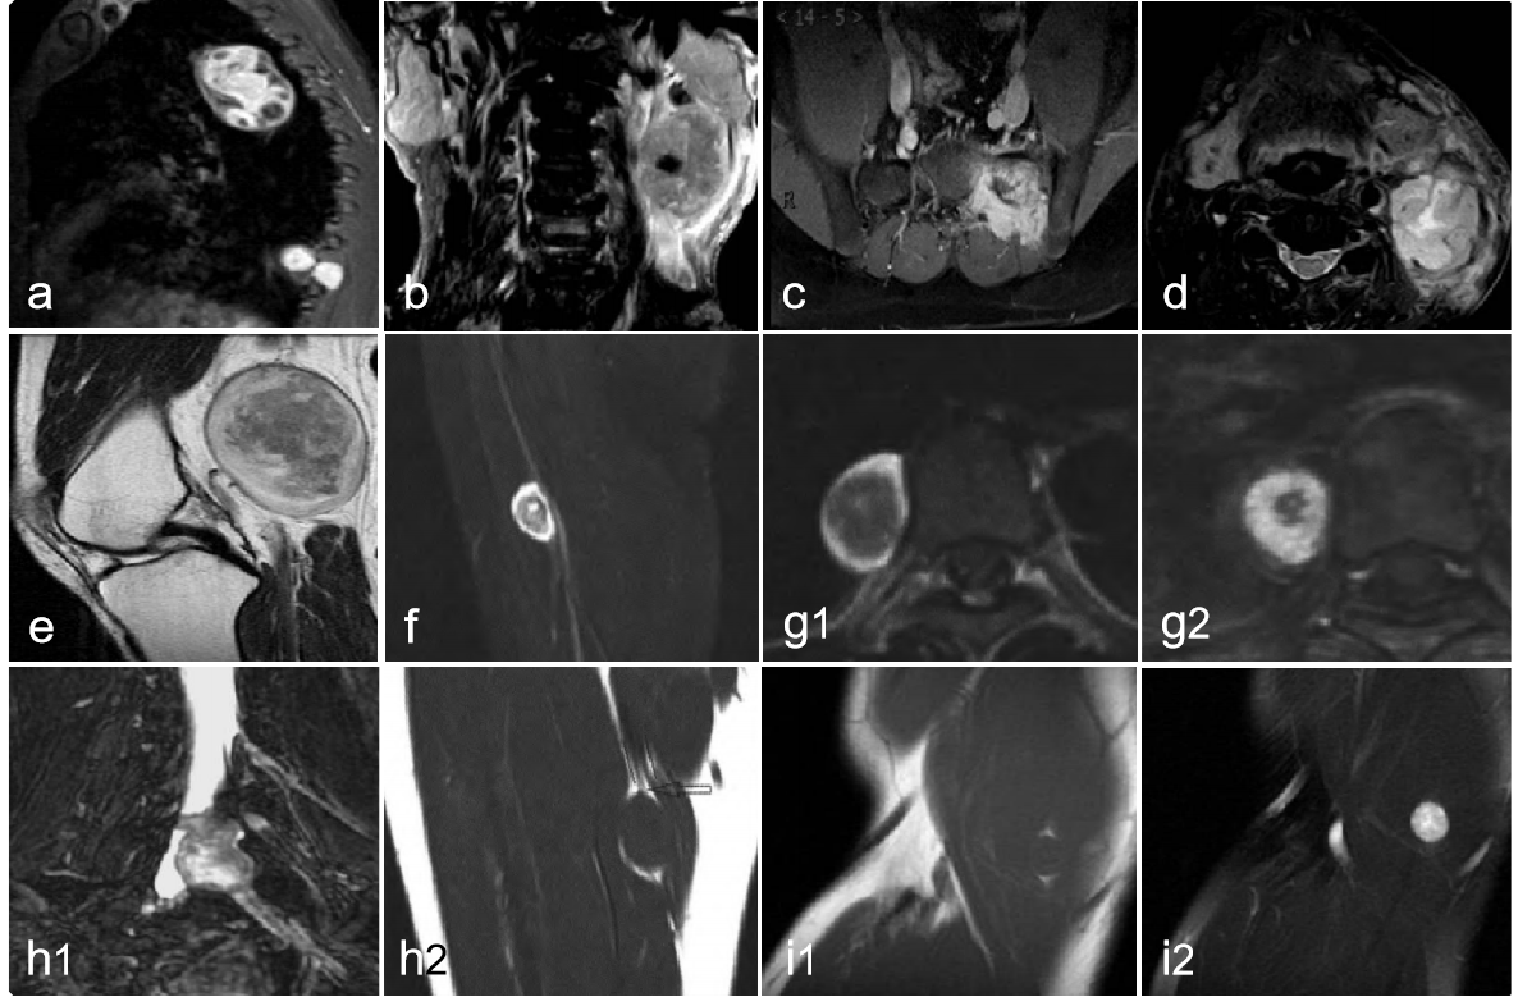

876c932d97c9df698f0d9b0c2123d636.png 病例 44:(腹膜后)副神经节瘤  47岁女性,体重减轻、腹痛和坐骨神经痛(a) 增强CT图像显示主动脉分叉水平肿块,中央坏死(*)和外周明显强化 (箭)。(b, c) T2WI及T1WI+C显示中央高信号坏死区(*)和明显的周边强化。(d) 大体病理显示边界清楚的包裹性肿块,病灶中央有粘液样和凝胶状成分(*),周围有红色出血(**)和黄色坏死区(箭头)。大口径血管(肠系膜下动脉)被肿瘤完全闭塞(箭)。(e) 镜下显示典型的zellballen生长模式,肿瘤细胞巢(*)被纤维血管隔 (箭头) 包围(HE×40)。(f) 高倍镜下显示嗜酸性粒细胞的细胞质、具有核仁的中央核和核内假包涵体(箭头)(HE×400)。